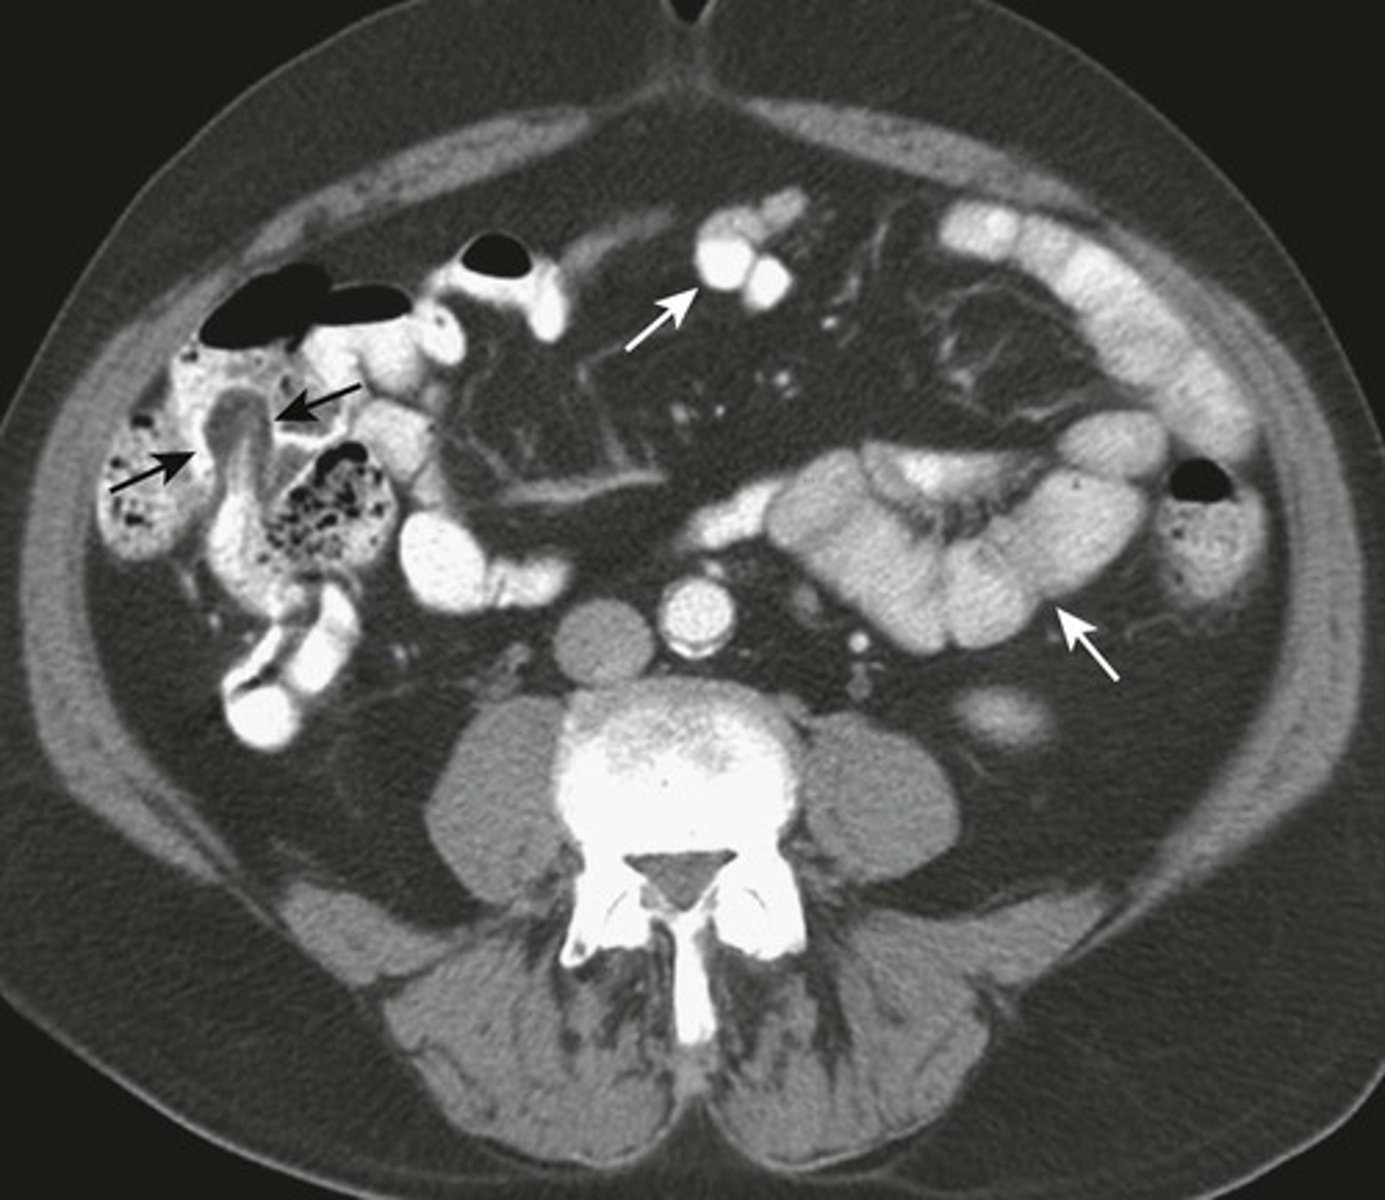

NORMAL Small bowel and large bowel.

WHITE ARROWS: small bowel

BLACK ARROW: Terminal ileum, recognized by fat-containing "lips" of the Ileocecal valve